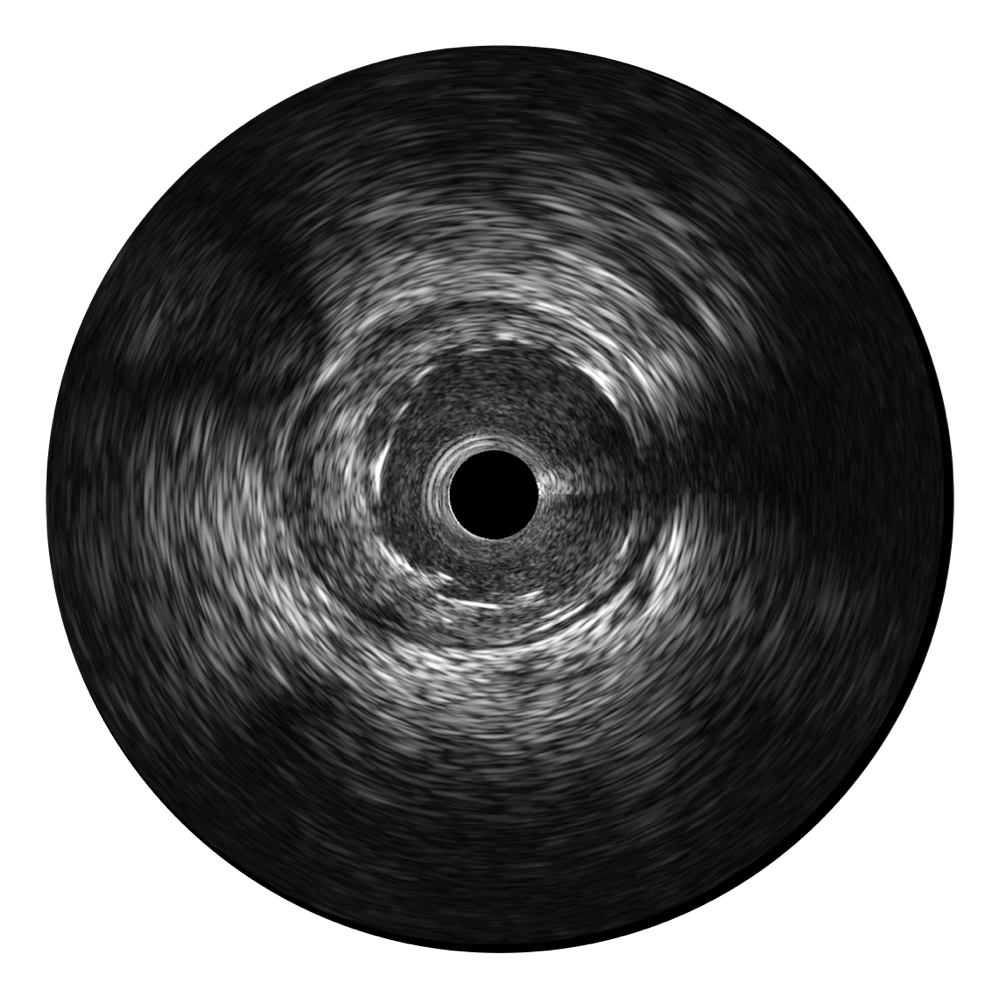

传统IVUS图像

对比传统IVUS导管成像,乐玩lewin国际宽频IVUS图像的近场支架梁显影更细腻,远场中膜外血管仍清晰可辨,兼顾远中近,兼顾分辨力与穿透深度